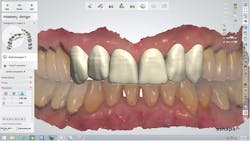

When the color was turned back on, the patient easily viewed and understood the 3-D digital diagnostic plan, which involved placing lithium disilicate (IPS e.max CAD, Ivoclar

Vivadent) crowns on teeth Nos. 6 through 11 (figure 5). The treatment goals were explained in a very efficient and effective manner, and understood by the patient. Major potential complications and the possibility of pulp exposure during tooth preparation of both laterals were also explained, after which the patient accepted the treatment plan and scheduled the first clinical appointment.

Figure 5: With the color turned back on, the patient easily understood the 3-D digital diagnostic plan.